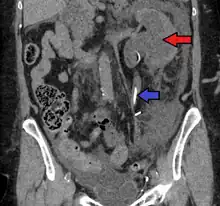

Massive hydronephrosis as marked by the arrow.- Renal ultrasonography of hydronephrosis[14]

- Stone causing hydronephrosis[14]

- Urine jets[14]